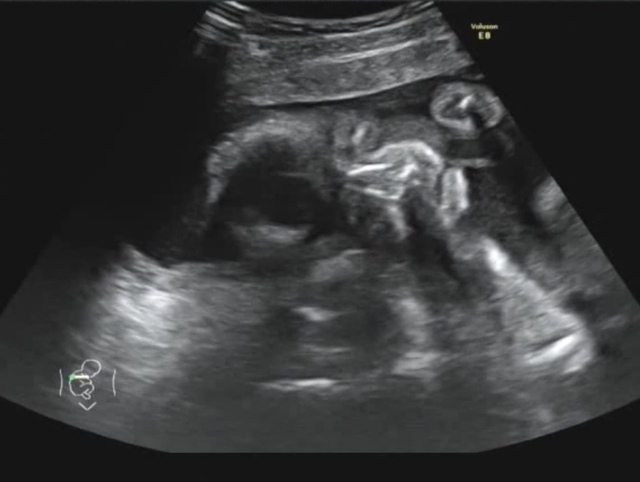

25週2日(25w2d・男の子)|May33 さん(29歳)

エコー写真撮影時のエピソード:

はじめて顔のパーツがはっきりワカルヨウナ正面からのエコー写真が撮れてとても嬉しくて、すぐに旦那さんにLINEで送りました。みんなからは目が大きいんじゃない?と言われてとても嬉しかったです。この頃は胎動がハッキリと分かるようになってきて、お腹も膨らんでいたので赤ちゃんが居ることを実感できるのが嬉しかったです。